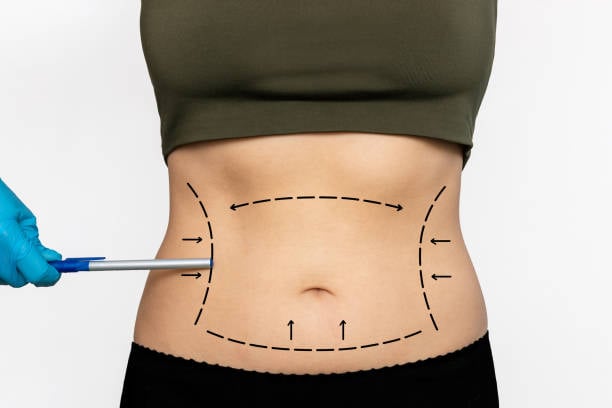

يسعى الكثير من الأشخاص إلى تحقيق جسم متناسق وصحي،وشفط الدهون في الرياض يُعد من أفضل الخيارات المتاحة لتحقيق هذا الهدف. بفضل التطور الطبي والتقنيات الحديثة، أصبح من السهل التخلص من الدهون الزائدة بفعالية وأمان. في هذا المقال، سنتناول بالتفصيل ما تحتا...

تعتبر عملية شد البطن في الرياض من أكثر الإجراءات التجميلية طلبًا في السعودية، حيث يسعى الكثيرون للحصول على بطن مشدود وجسم منحوت بعد فقدان الوزن أو بسبب التغيرات التي تطرأ على الجسم نتيجة الحمل أو الشيخوخة. في هذا المقال، سنقدم لكِ دليلًا شاملاً حول أ...

تعد شفط الدهون في الرياض واحدة من أكثر العمليات التجميلية شيوعًا للأفراد الذين يسعون إلى تحسين مظهرهم واستعادة رشاقتهم. تقدم هذه التقنية حلاً فعالًا لإزالة الدهون العنيدة التي قد يصعب التخلص منها بالحمية أو التمارين الرياضية. في هذا المقال، سنناقش كي...